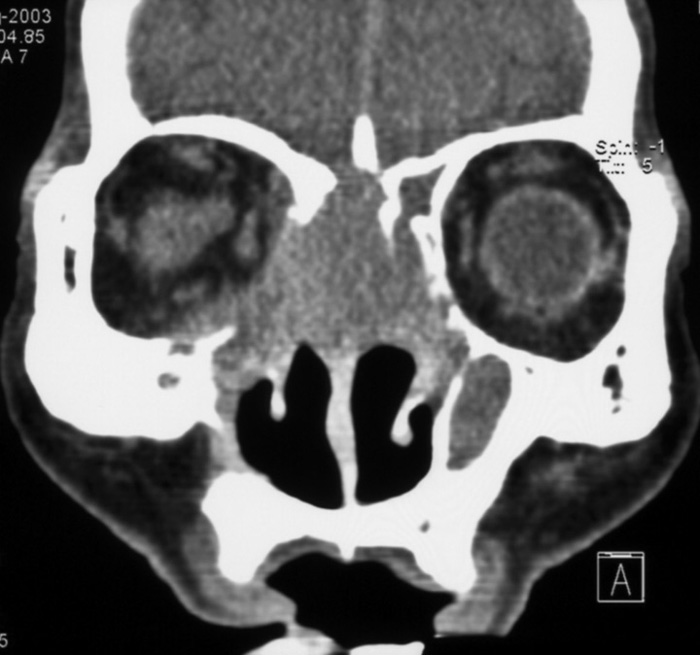

症例6:71歳男性

1993年、右蝶形骨洞嚢胞による圧排に伴う視力低下あり。嚢胞開放術施行。

1996年、蝶形骨洞嚢胞再発により再手術。

2ヶ月前(2003. 6)より右視力低下、視野障害及び頭痛出現。蝶形骨洞嚢胞再々発が疑われ、当院耳鼻科受診。

蝶形骨洞腔は鼻腔との交通あり、嚢胞再発は否定的。

図1